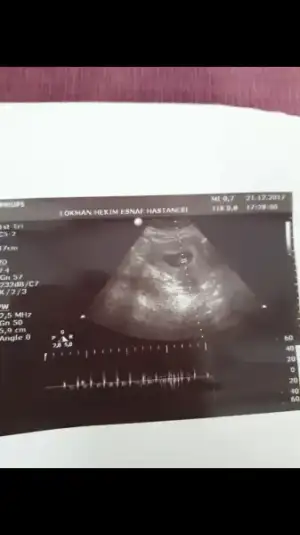

Gercekten en onemlisi saglik zaten cok zor hamile kaldim ukalalik yapmak istemiyorum ille de kiz kiz diye .Ben hamileliğimi öğrenince hep şunu dedim erkek diye insanın içine doğuyor ama ben kız istiyordum neyse sağlık versin rabbim